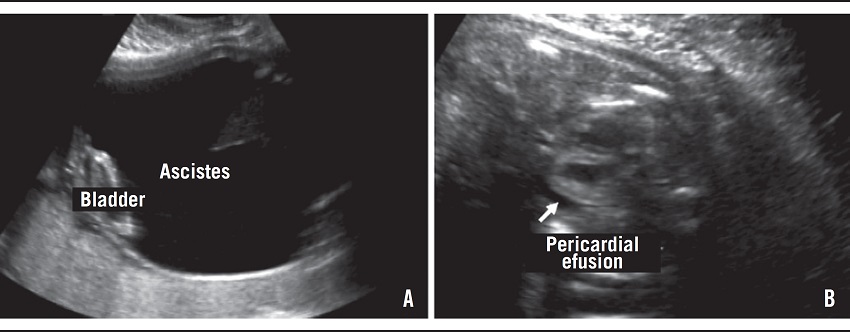

V. G. was a 21-year-old pregnant woman for the first time referred for the high-risk prenatal care due to an alteration in obstetrical ultrasound. There was an image suggestive of megabladder. The 20-week ultrasonography (USG) examination showed absence of the amniotic fluid (anhydramnios) and an enlarged bladder with narrowing of the urethra in the proximal region, suggestive of lower urinary tract obstruction (LUTO). At 21 weeks of gestation the fetal bladder was punctured for relief of obstruction, and biochemical and karyotype analysis of the material was performed. The volume of fetal urine removed was 282 ml. There were no complications during or after the procedure. The karyotype was normal (46,XY). The biochemical analysis showed the following results: potassium: 3 mEq/l (reference value: < 3 mEq/l); sodium: 109 mEq/l (reference value: < 100 mEq/l), and chlorides: 93 mEq/l (reference value: < 90 mEq/l), indicative of renal damage. Second-trimester ultrasound showed absence of amniotic fluid; increased echogenicity of the renal parenchyma, and distended bladder with "keyhole signal" (Figure 1). Fetal echocardiography was normal. The 25-week ultrasound also showed severe ascites, pericardial effusion, fetal bladder walls thickening, and the right kidney with diminished dimensions (Figure 2). The infant was born through vaginal delivery, at 27 weeks of pregnancy, weighing 1,960 grams and Apgar scores of 1 at first and fifth minutes. The infant had a significant abdominal distention and upper and lower limb deformities (Figure 3). He presented respiratory distress and evolved to death about 2 hours after birth.